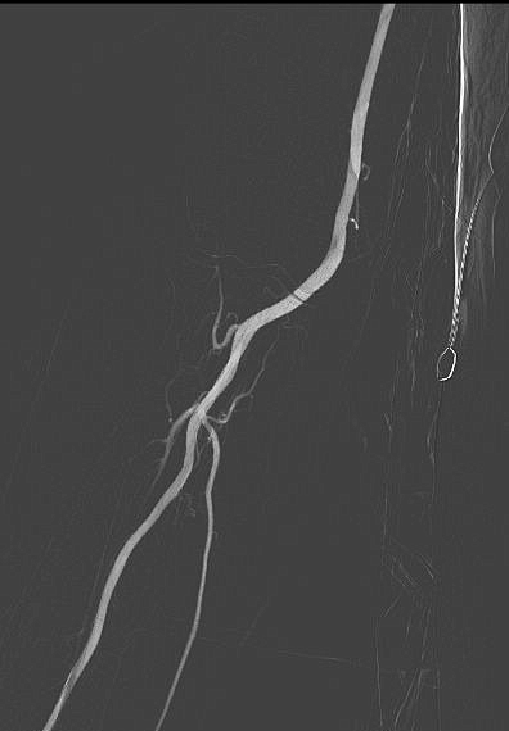

球扩后造影支架成形好,无残余狭窄,椎动脉显影

术前左侧锁骨下起始段重度狭窄

术后狭窄解除,血管恢复正常形态